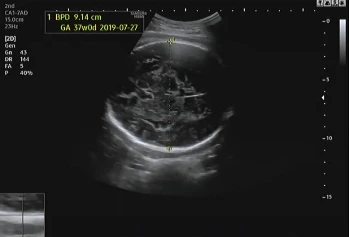

임신 39주 4일 차 병원에 내원해 초음파를 확인했다. 지난번에 이어 큰 이상이 없어 2주 뒤에 내원했는데 다행히 태아도 그동안 건강함을 알려주듯 초음파를 보는 내내 열심히 움직였다.